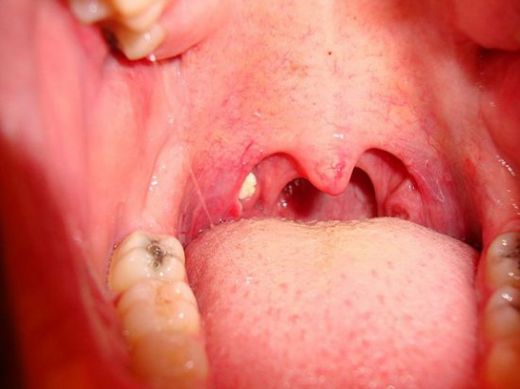

- Cerrahi müdahale: Tekrarlayan bademcik iltihabı durumunda, bademciklerin cerrahi olarak alınması (tonsilektomi) düşünülebilir.

- 29 Eylül 2024 Pazar

Tek Bademcik Şişmesi Belirtileri ve Tedavisi- 28 Eylül 2024 Cumartesi